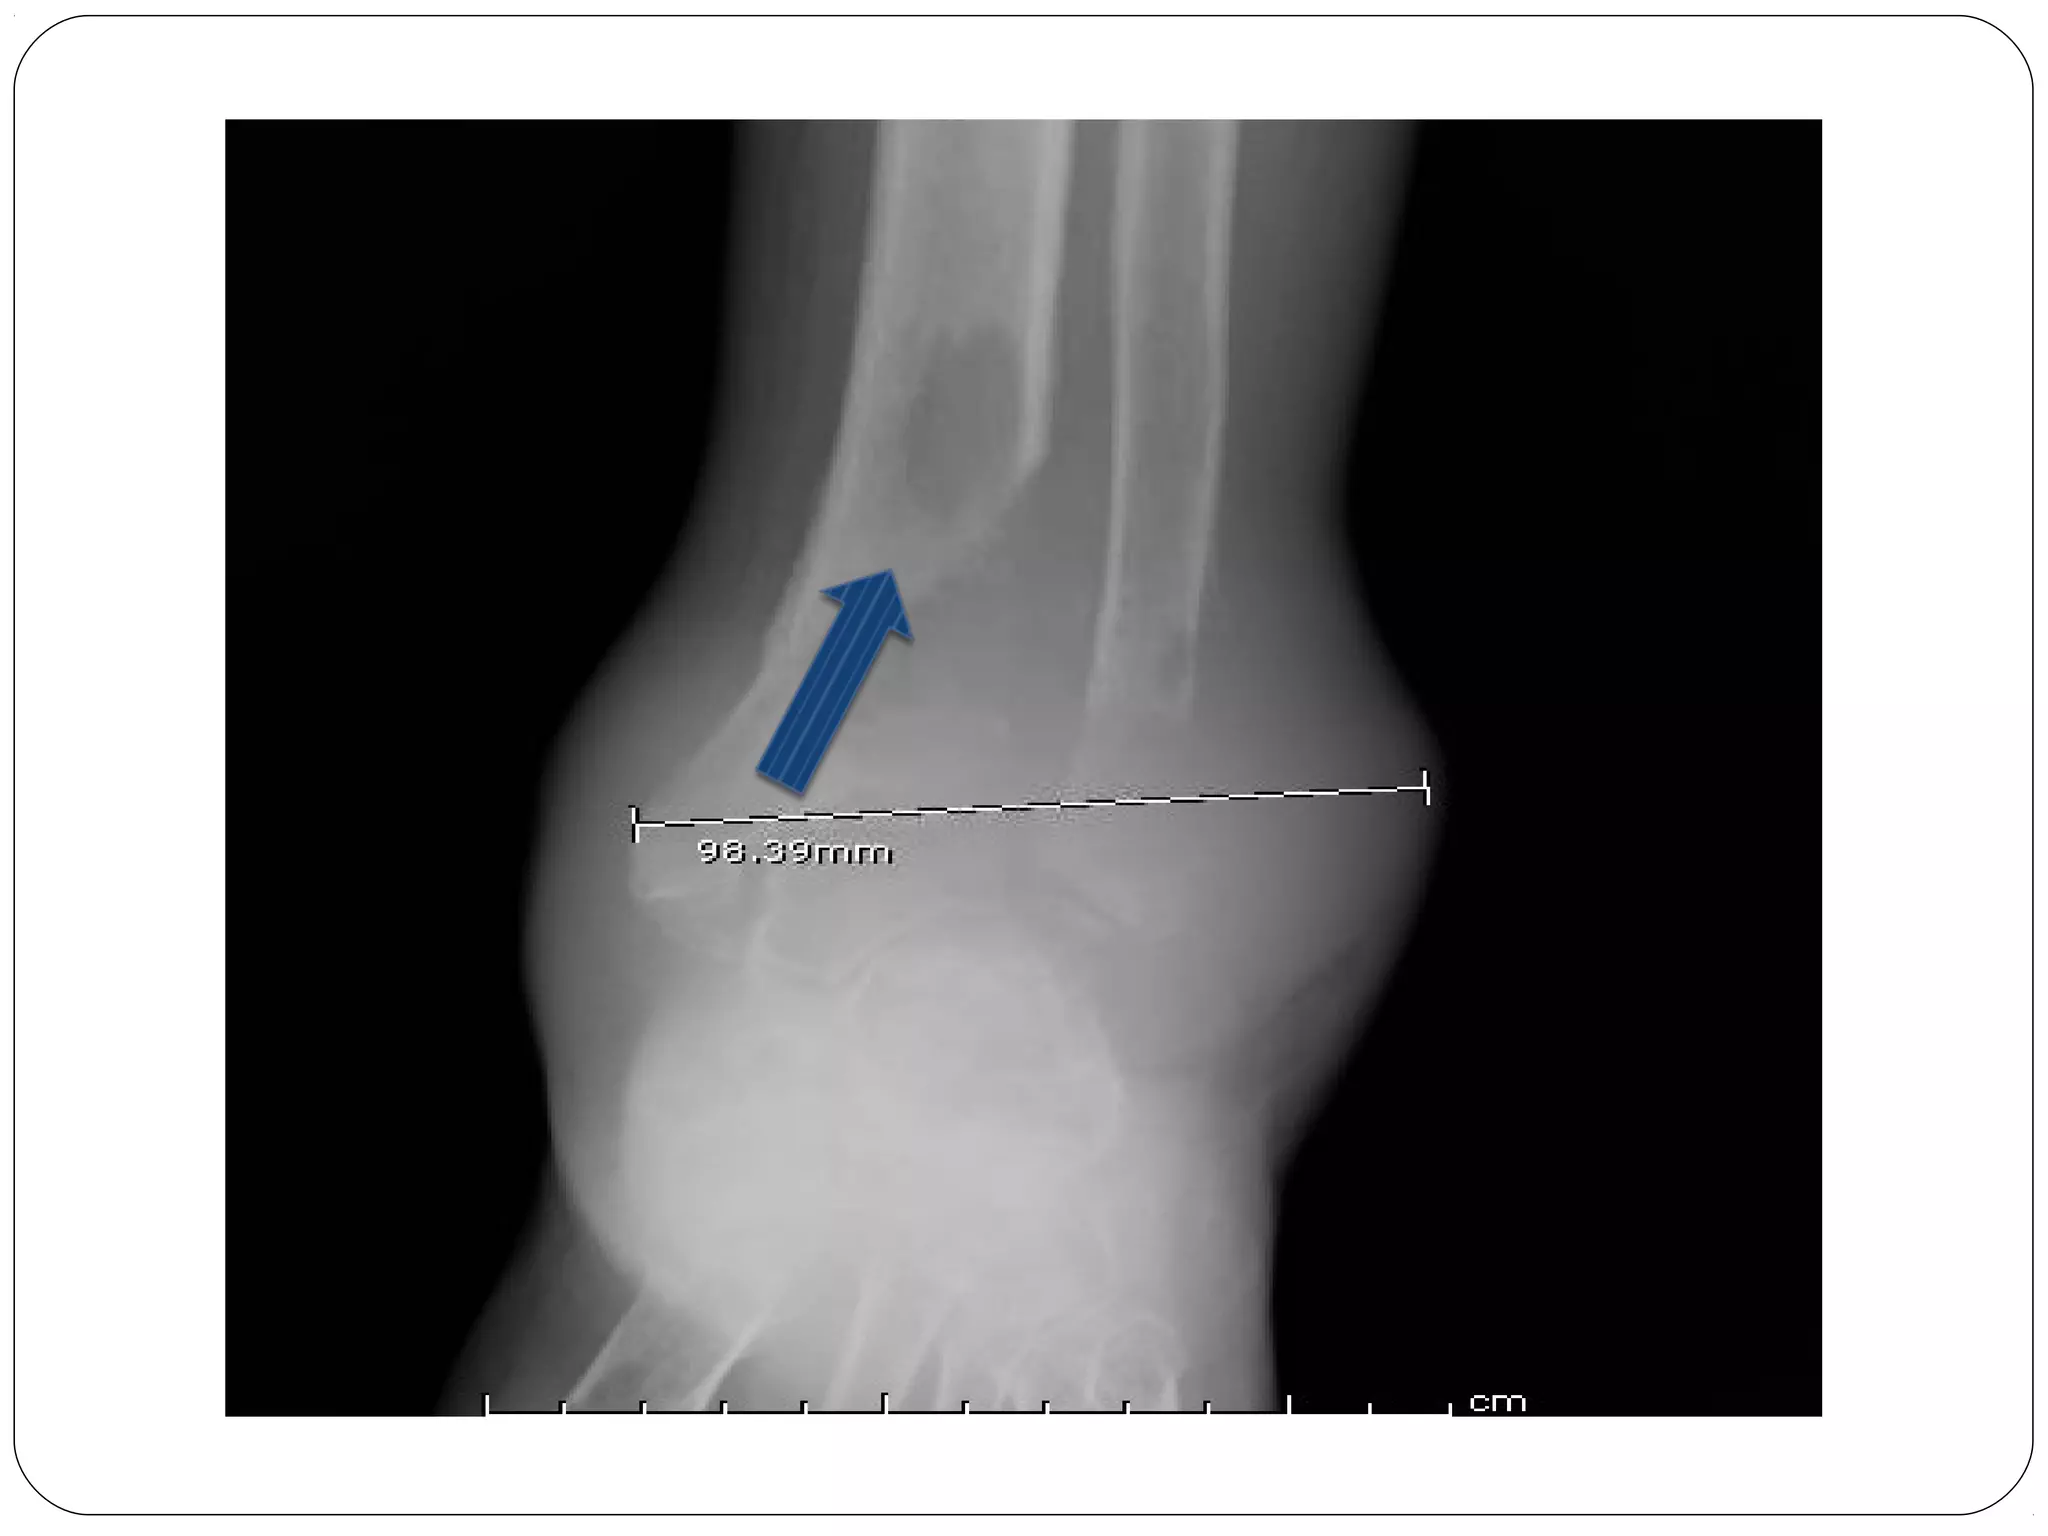

A-B-C-D

A- Alignment- is the bone in good general

Alignment